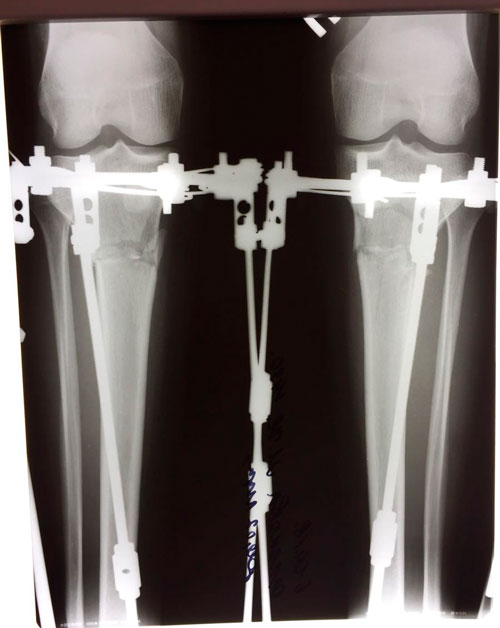

Перед крутками.

Вложения

IMG-20180323-WA0004.jpg